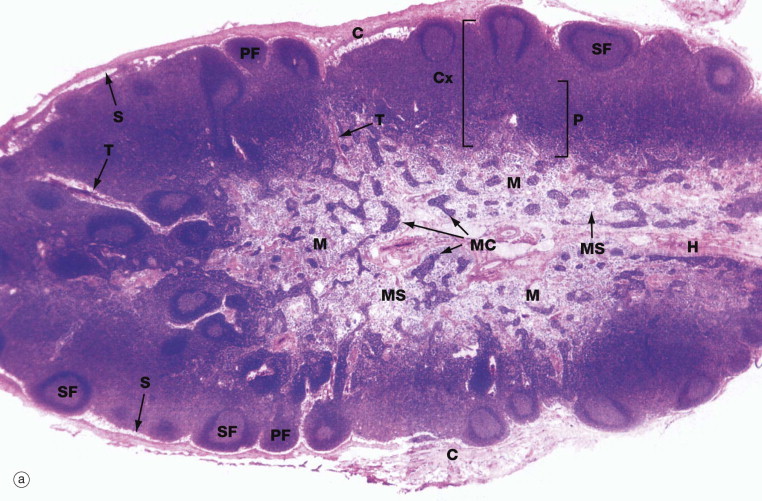

Thymus, cortex, medulla

Name the structures

Spleen

White Pulp

Red Pulp